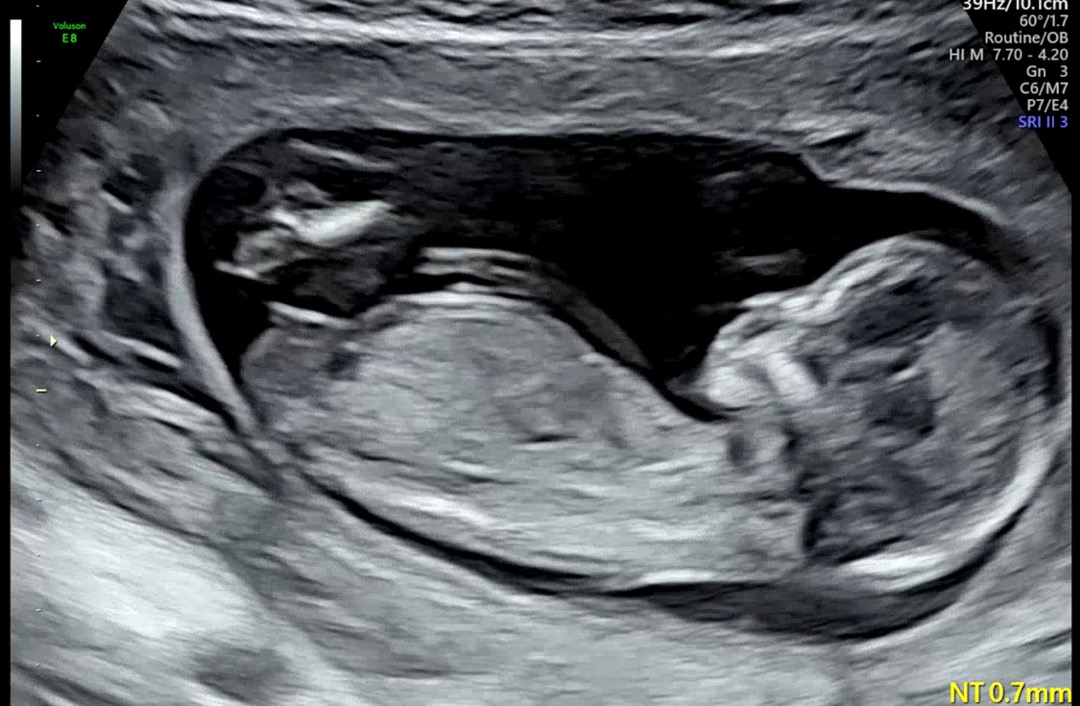

1차 기형아검사 초음파

안녕하세요! 1차 기형아검사 사진입니다. 크기는 13주 주수라고 하시더라구요 ㅎㅎ 혹시 성별 예측 가능할까요….?!